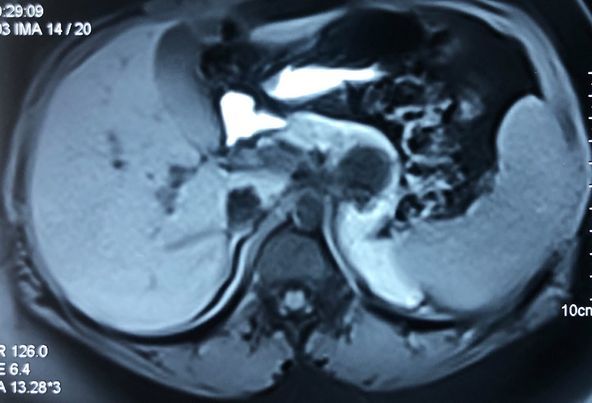

Child’s A CLD with HUGE gastric varices uncontrolled by Endoscopic glue and attempted EUS coiling. One salvage option would be TIPSS with balloon vascular occlusion but due to logistics we went for modified sugiura procedure. Splenectomy + Gastro esophageal devascularisation with anterior Gastrotomy and overseeing of gastric varices with pyloroplasty. Images show 1 CECT showing large gastric fundal varices. 2,3,4 Gastro Esophageal devasc 5, 6 Large fundal varices before and after oversewing. 7. Anterior gastrotomy 8. Pyloroplasty. Postoperative recovery was uneventful.